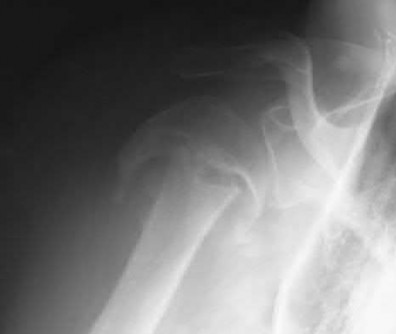

1024) An 18-year-old football player crossing the field to make a catch is hit on the shoulder and upper chest by the tackler and falls to the

ground with immediate pain throughout the shoulder region. The emergency department physician obtains the radiographs, CT scan, and 3-dimensional reconstructions seen in Figures 118a through 118e. What is the next step in management?

Corrent answer: 4

The player has sustained a posterior sternoclavicular dislocation. The CT scans show the medial end of the clavicle in close proximity to the aorta. An MRI scan will add no diagnostic information and might delay treatment. Nonsurgical management of an anterior sternoclavicular dislocation is often appropriate, but given the proximity of the clavicle to the aorta and airway, reduction of the dislocation is recommended to prevent vascular injury. While reduction is indicated, performing the reduction in the emergency department is not recommended because of the vascular injury or the need to perform an open reduction. Performing the procedure in the operating room with a thoracic surgeon available is recommended. Usually a closed reduction is stable, but if open reduction is necessary, Kirschner wires should be avoided to avoid the chance of migration of the implants.